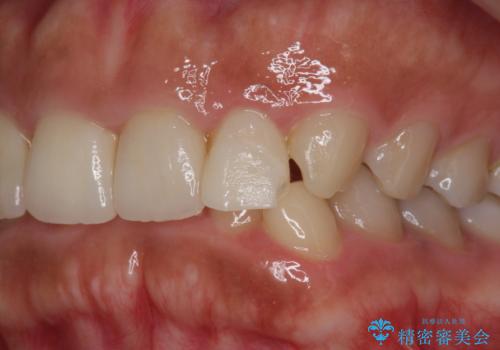

- 他院で昨年治療したセラミッククラウンが欠け、審美性の改善を求めて来院されました。

噛み合わせからクラウンが欠けやすい状態だったので、欠けにくく強度に優れるフルジルコニアクラウンで審美性を改善します。

フルジルコニアクラウンは若干透明感に劣る反面、強度に優れ大きな力のかかる部位に有効な補綴方法です。